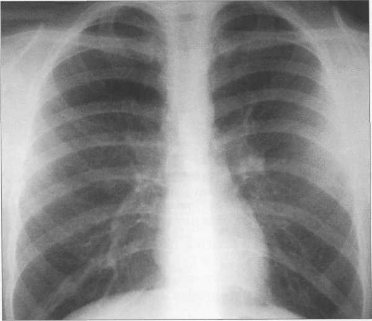

У новорожденных сердце имеет относительно большую величину, СЛК у них может достигать 58% (рис. 9.22). У более старших детей и у взрослых СЛК составляет 44—48%, для большого числа подростков характерны небольшие размеры сердца (СЛКменее 40%) (рис. 9.23),улюдей пожилого возраста поперечные размеры сердца увеличиваются, СЛК у них, как правило, более 50%.

Рис. 9.23. Рентгенограмма грудной клетки подростка. Передняя проекция.